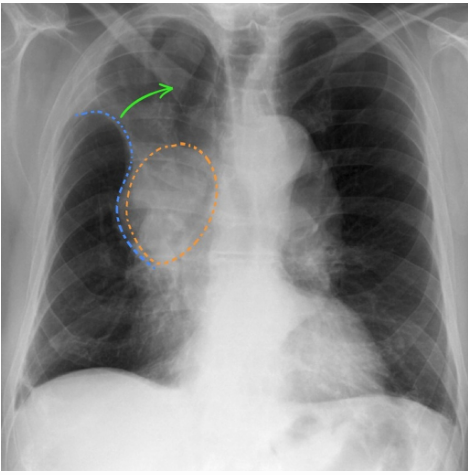

The following CXR is highly suggestive of what restrictive pulmonary pathology in a ~ 50 year old man? _____

_____ sign is a radiographical appearance seen in the right upper lobe collapse in bronchogenic carcinoma.

The following sign is also known as _____ sign